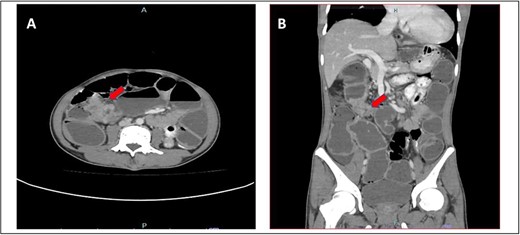

A 52-year-old Malay man, an active smoker, with underlying pulmonary hypertension secondary to atrial septal defect secundum with Eisenmenger syndrome and chronic lung disease. He had been experiencing symptoms of intestinal obstruction for a week. He had abdominal pain for 1 day, vomiting for 2 days, and unable to pass motion for the past 1 week. Patient was tachypnoeic with a respiratory rate of 35/min, a pulse rate of 116 bpm, and SPO2 of 90% under high-flow nasal cannula 50%/50 L. Abdominal radiograph showed dilated large bowel. Computed tomography abdomen and pelvis revealed short segment circumferential enhancing bowel wall thickening at rectosigmoid region causing intraluminal obstruction and presence of target sign at left lumbar region suggestive of jejunojejunal intussusception (Figs 2 and 3).

(A) Axial view and (B) coronal view of computed tomography showed presence of doughnut sign at left lumbar region suggestive of jejunojejunal intussusception (red arrow).